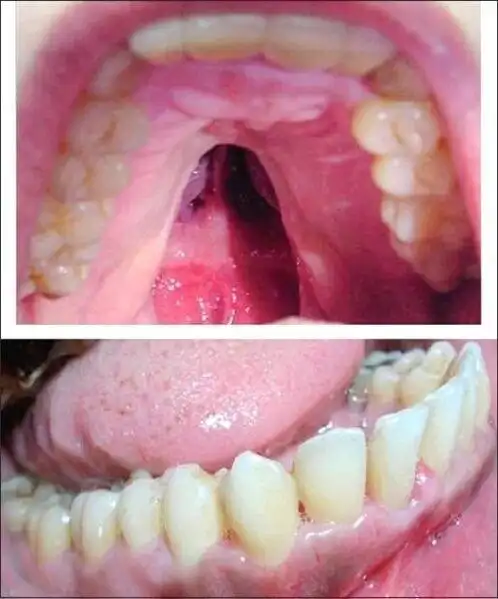

软腭裂是什么症状